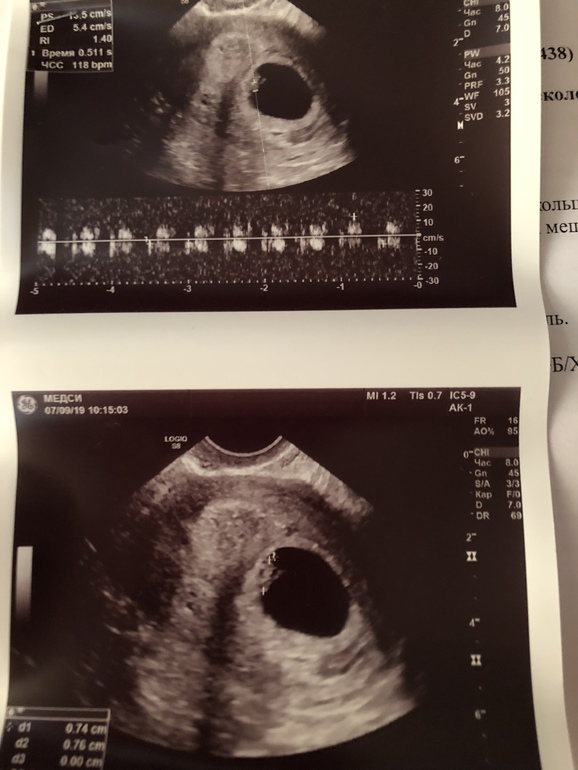

Нас нашли!! В 6 и 1 ! И сердечко!! Девочки,всем спасибо огромное за поддержку!